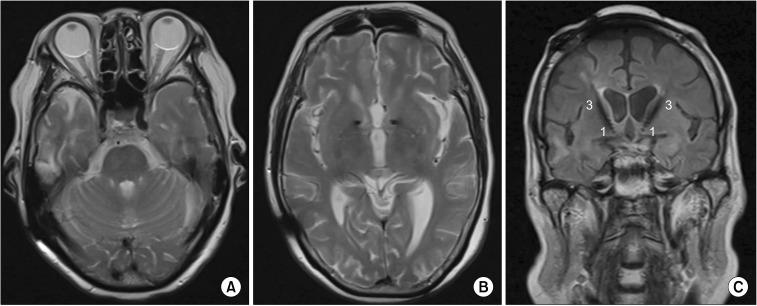

Psychiatric symptoms are common after traumatic brain injury (TBI), and some patients have poor drug therapeutic efficacy. We report a successfully treated case of psychiatric symptoms after TBI using deep brain stimulation (DBS) to the anterior limb of internal capsule (ALIC)-nucleus accumbens (NAc) in a 76-year-old woman. The patient suffered from auditory hallucination, mood changes, and insomnia caused by TBI. Psychological test assessment showed the scores of Hamilton Anxiety Scale, Hamilton Depression Scale and Positive and Negative Syndrome Scale were 30, 35, and 96 respectively. Head magnetic resonance imaging scan showed right temporal lobe encephalomalacia. Head magnetic resonance spectroscopy (MRS) showed bilateral basal ganglia choline increased relatively. After DBS to the ALIC-NAc, the target parameters were adjusted. The psychiatric symptoms were completely improved and the result of head MRS was normal in the end. The current report declares that DBS is reversible, adjustable and safe in the treatment of psychiatric symptoms caused by TBI. DBS to the ALIC-NAc should be considered as a possible treatment choice once a patient showed psychiatric symptoms after TBI.

精神症状在创伤性脑损伤(TBI)后很常见,一些患者药物治疗效果不佳。我们报告了一例76岁女性TBI后精神症状通过脑深部电刺激(DBS)内囊前肢(ALIC)-伏隔核(NAc)成功治疗的病例。该患者因TBI出现幻听、情绪变化和失眠。心理测试评估显示汉密尔顿焦虑量表、汉密尔顿抑郁量表和阳性与阴性症状量表得分分别为30、35和96。头部磁共振成像扫描显示右侧颞叶脑软化。头部磁共振波谱(MRS)显示双侧基底节胆碱相对增加。对ALIC-NAc进行DBS后,调整了目标参数。精神症状最终完全改善,头部MRS结果正常。本报告表明DBS在治疗TBI引起的精神症状方面具有可逆性、可调节性和安全性。一旦患者TBI后出现精神症状,应考虑将对ALIC-NAc进行DBS作为一种可能的治疗选择。